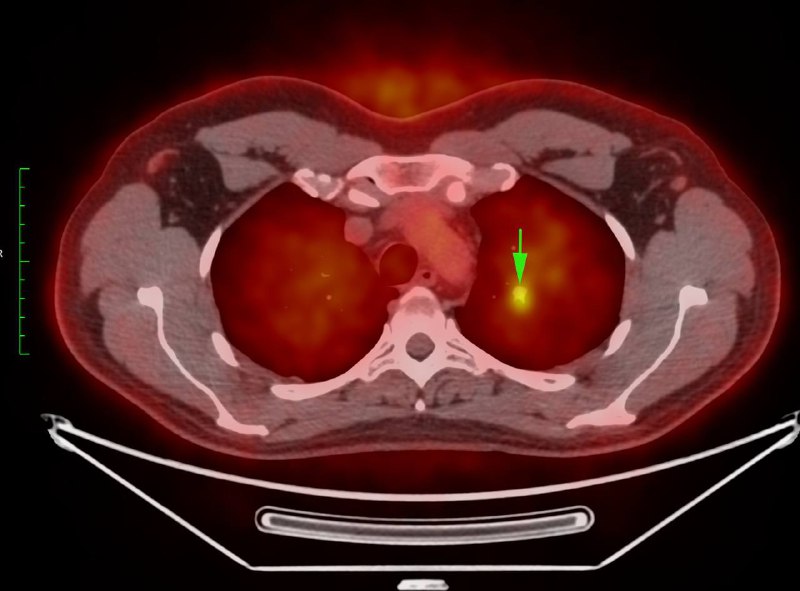

Взяли бы на себя наглость написать параганглиому блуждающего без дифа?